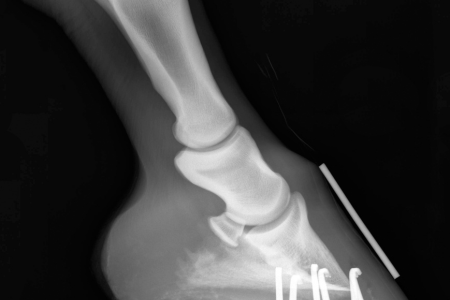

- Because every horse is different and shows discomfort differently, the only way to monitor rotation and sinking of the pedal bone is with regular X-rays. Measurements of structures inside the hooves can track progress and healing.

Radiographs show the relationship between the coffin bone and the hoof wall. When they are not parallel, something is amiss. This horse looks fine in that respect.

- Imaging like radiographs helps your vet see the bones and establish an injury baseline.

- X-rays will give your vet an accurate picture of the hoof’s bones and structures. These give your vet a baseline from which to monitor changes. Your farrier also needs these to provide support with corrective trimming, wedges, or special shoes. You can document the exterior and sole of the hoof with photos and notes.